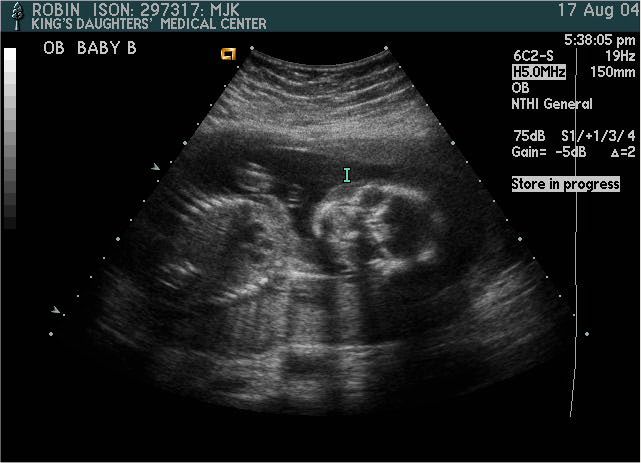

Baby B

Pictures from Ultrasound at 20 weeks.